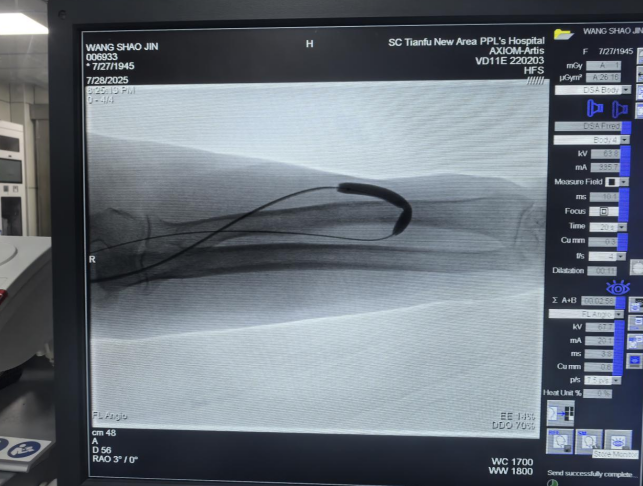

PTA是一种微创手术,是在DSA或超声引导下,经皮穿刺动静脉,送入球囊扩张导管,对血管的狭窄部分进行扩张,将闭塞的病变重新开通,以及去除血栓。

此手术具有精准、微创、安全、有效、操作简便、可重复性等优点,狭窄开通率高达95%以上,术后当天即可恢复透析,因此球囊扩张术是国际公认的通路狭窄首选治疗方案,能为血液透析患者重新疏通“向生之路”。

获知该技术的优势后,7月28日,汪女士接受了“无痛”的DSA下动静脉内瘘狭窄球囊扩张术。在整个手术过程中,汪女士只感受到一定的压力,但疼痛明显被有效控制。术后,汪女士表示,本次术中“无痛”体验与上次局部麻醉的感受可谓天壤之别。术后第二天,她就顺利地接受了常规血液透析。